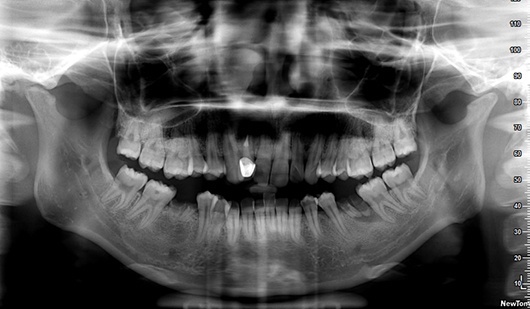

首先第一个是因为六龄齿已经蛀到只剩残根,拔除后我们打算把第二磨牙和智齿前移,关闭拔牙间隙,使智齿变废为宝。

智齿的存在我们看X光片就可以预计它能否顺利萌出,如果阻生,应该尽早拔除。

智齿的存在也是后牙段拥挤的始作俑者,我们眼睛往往只着重于前牙拥挤,没有看到后牙如果有倾斜、扭转等等也是拥挤的表现。